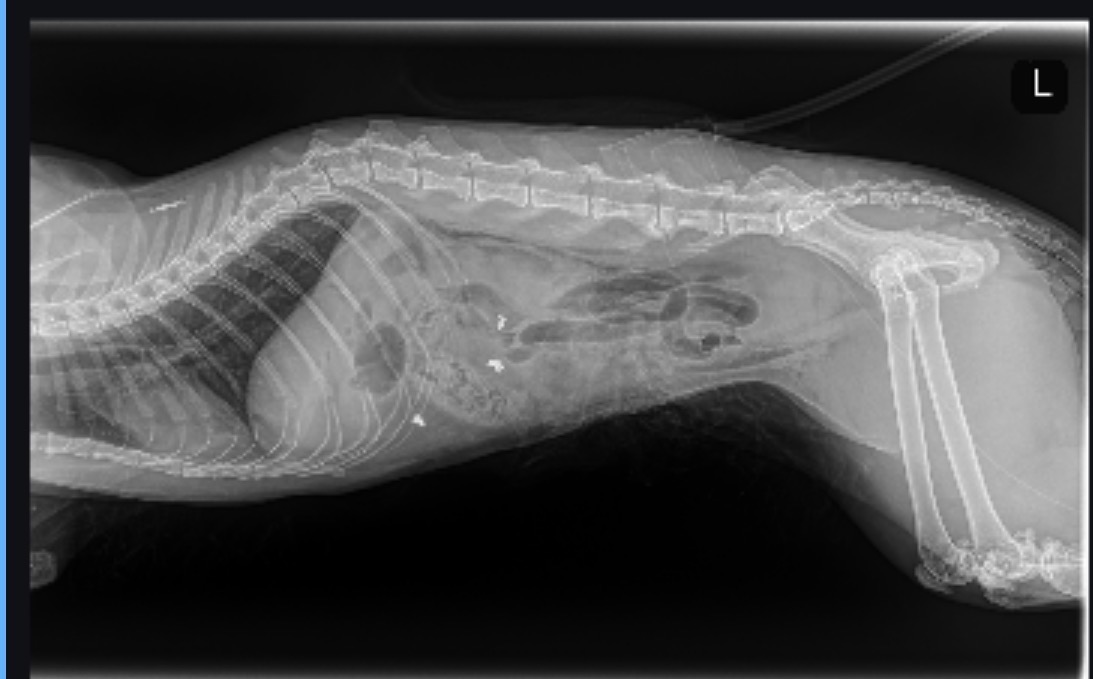

A few hours later, we received devastating news, Autumn hadn’t injured himself. He had been shot with a .22 caliber bullet.

We were heartbroken and angry. We checked our cameras and saw that he came inside from our cat patio around 12 PM, but by the time we found him at 7 PM, he had been silently fighting for his life for hours.

Autumn is now under critical care at Eclipse Emergency Vet Clinic. Despite everything he’s been through, he is still fighting. Every small sign,every movement, every stable moment, tells us he wants to live.